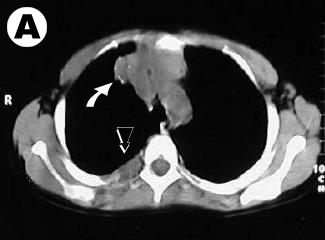

Corte tomográfico

en tercio superior del torax:

• Flecha Blanca: Lesión mediastinal, lobulada, sólida e irregular con micro - calcificaciones.

• Flecha Negra: Lesion tumoral con destrucción ósea del 3er. arco costal posterior

• Corte tomografico se aprecia la lesion mediastinal y osea costal porterior

Corte tomografico: tumor mediastino y lesion costal posterior